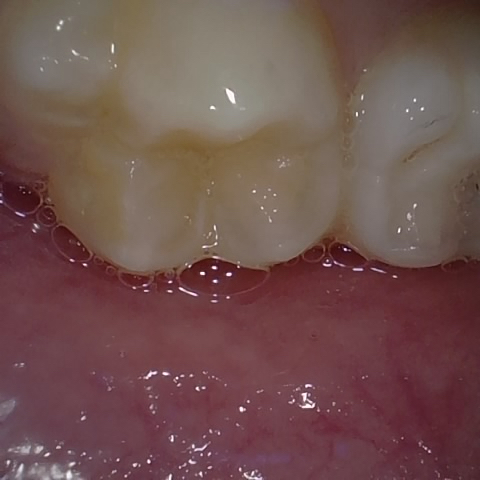

Annotated as "Good"